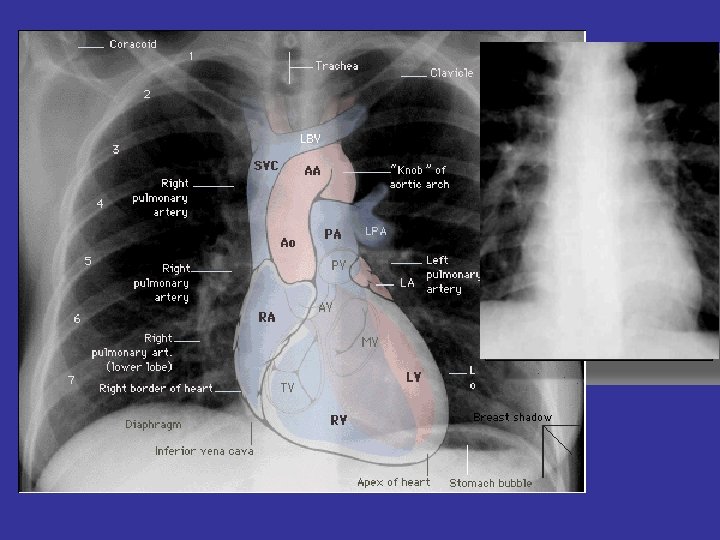

* trachea ; position & caliber * hila : lymphadenopathy * mediastinum contour

* trachea ; position & caliber * hila : lymphadenopathy * mediastinum contour : ? mass * heart : cardiac configuration Mediastinum, heart and hila

How to read a chest x ray ? • 1 - chest wall, bones

How to read a chest x ray ? • 1 - chest wall, bones and abdomen * bones; lesions or fractures * soft tissue ; mastectomy or soft tissue tumors • 2 - heart and mediastinum * trachea ; position & caliber * hila : lymphadenopathy * mediastinum contour : ? mass * heart : cardiac configuration • 3 - lungs opacity or lucency